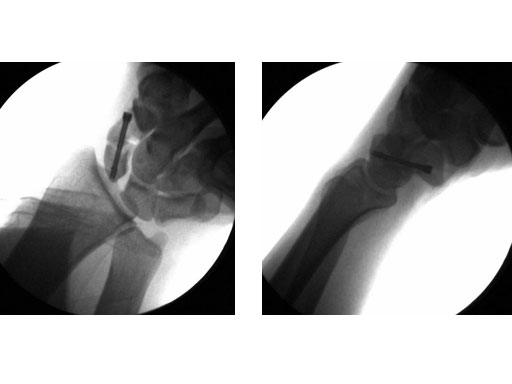

24-year-old male with an acute scaphoid wrist fracture treated by percutaneous fixation with a 3.0 mm headless compression screw under regional anesthesia.

Fig 1 Preoperative x-ray.

Fig 2ab Intraoperative images.